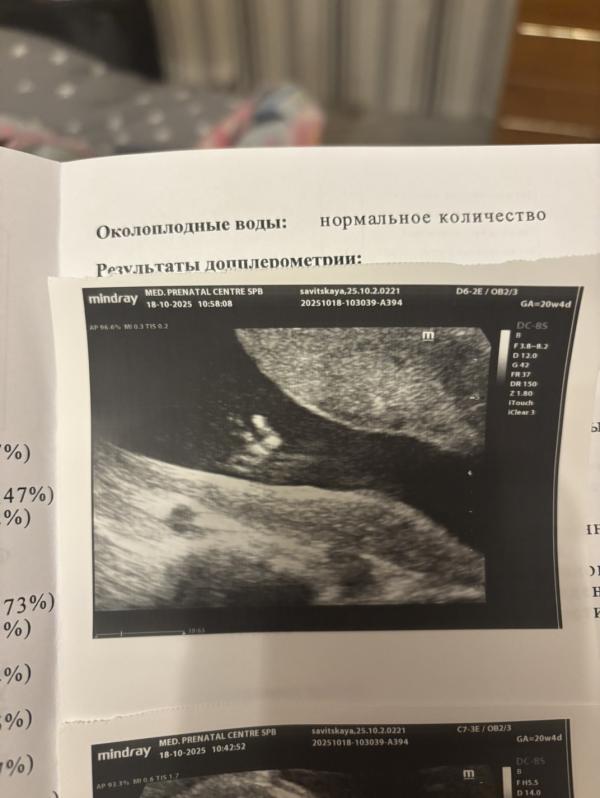

Девочки,сделала скрин из видео со 2 скрининга ( бесплатного ) , там где врач не увидел фаланг на мизинце.

Что скажете ?

Вправду не видно , или я себе накручиваю,что он есть?☹️